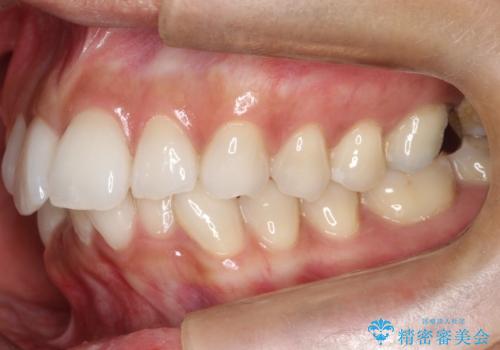

【インビザライン】前歯の凸凹をIPRで改善

- 前歯の凸凹を主訴に来院されました。

前歯を並べるために歯と歯の間にヤスリを入れてわずかに歯を削ることでスペースを確保しています。

歯と歯の間にヤスリを入れてわずかに歯を削ることでスペースを確保する処置をIPRと呼びます。

当院では拡大鏡を用いて丁寧に処置することで歯冠形態を損なわずに行うことができます。